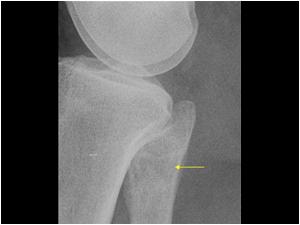

Apxe Brodie

Apxe Brodie + Mất liên tục màng xương

Apxe Brodie + Mất liên tục màng xương - Phù nề mô mềm

Viêm xương tủy

» Thông tin: Nam giới – 34 tuổi.

» Lâm sàng: Sưng đau khớp gối.

# Apxe Brodie / Mất liên tục màng xương – Phù nề mô mềm.